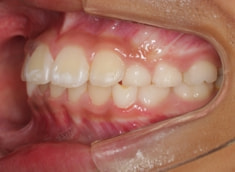

治療後(1年1ヶ月後)